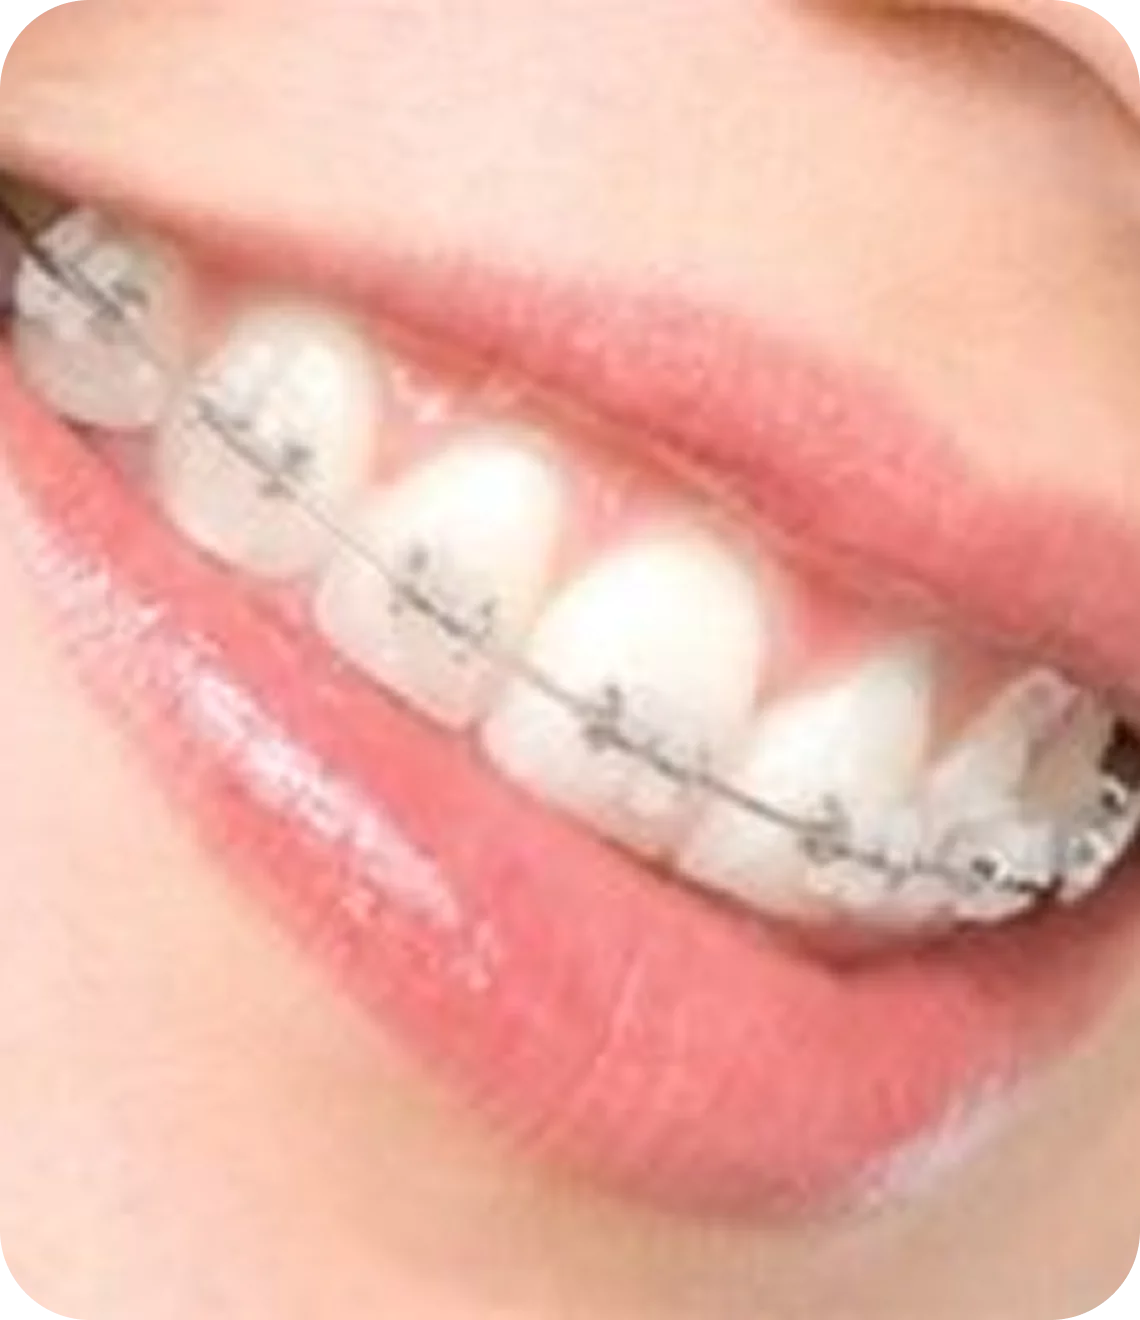

steel braces

The most common and recognizable braces are the stainless steel braces. These braces are very durable and different color ties may be used with them for decorative purposes to enhance the orthodontic experience.